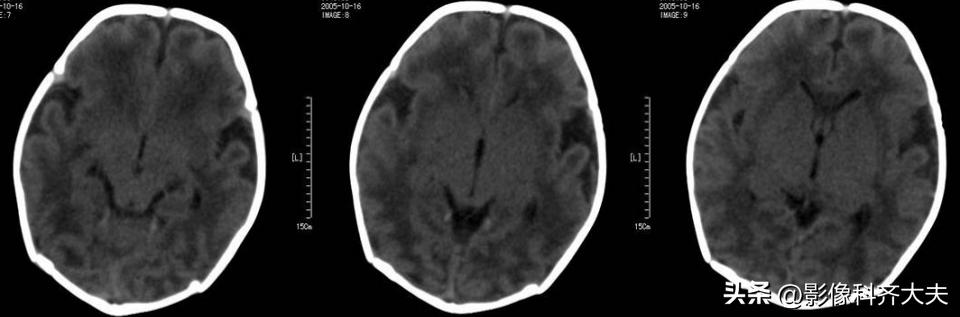

HIE的CT表现

1、测定脑实质的CT值,正常足月儿脑白质CT值在20Hu以上,≤18Hu为低密度

2、脑水肿时呈双侧大脑半球呈弥漫性低密度伴脑室变窄

3、基底核和丘脑损伤时呈双侧对称性高密度影

4、脑梗死表现为相应供血区呈低密度

CT分度

1、轻度:散在局灶低密度影分布2个脑叶内。

2、中度:低密度影超过2个脑叶,白质灰质对比模糊。

3、重度:弥漫性低密度影,灰质白质界限消失,但基底节、小脑尚有正常密度。

注:中、重度常伴有颅内出血。